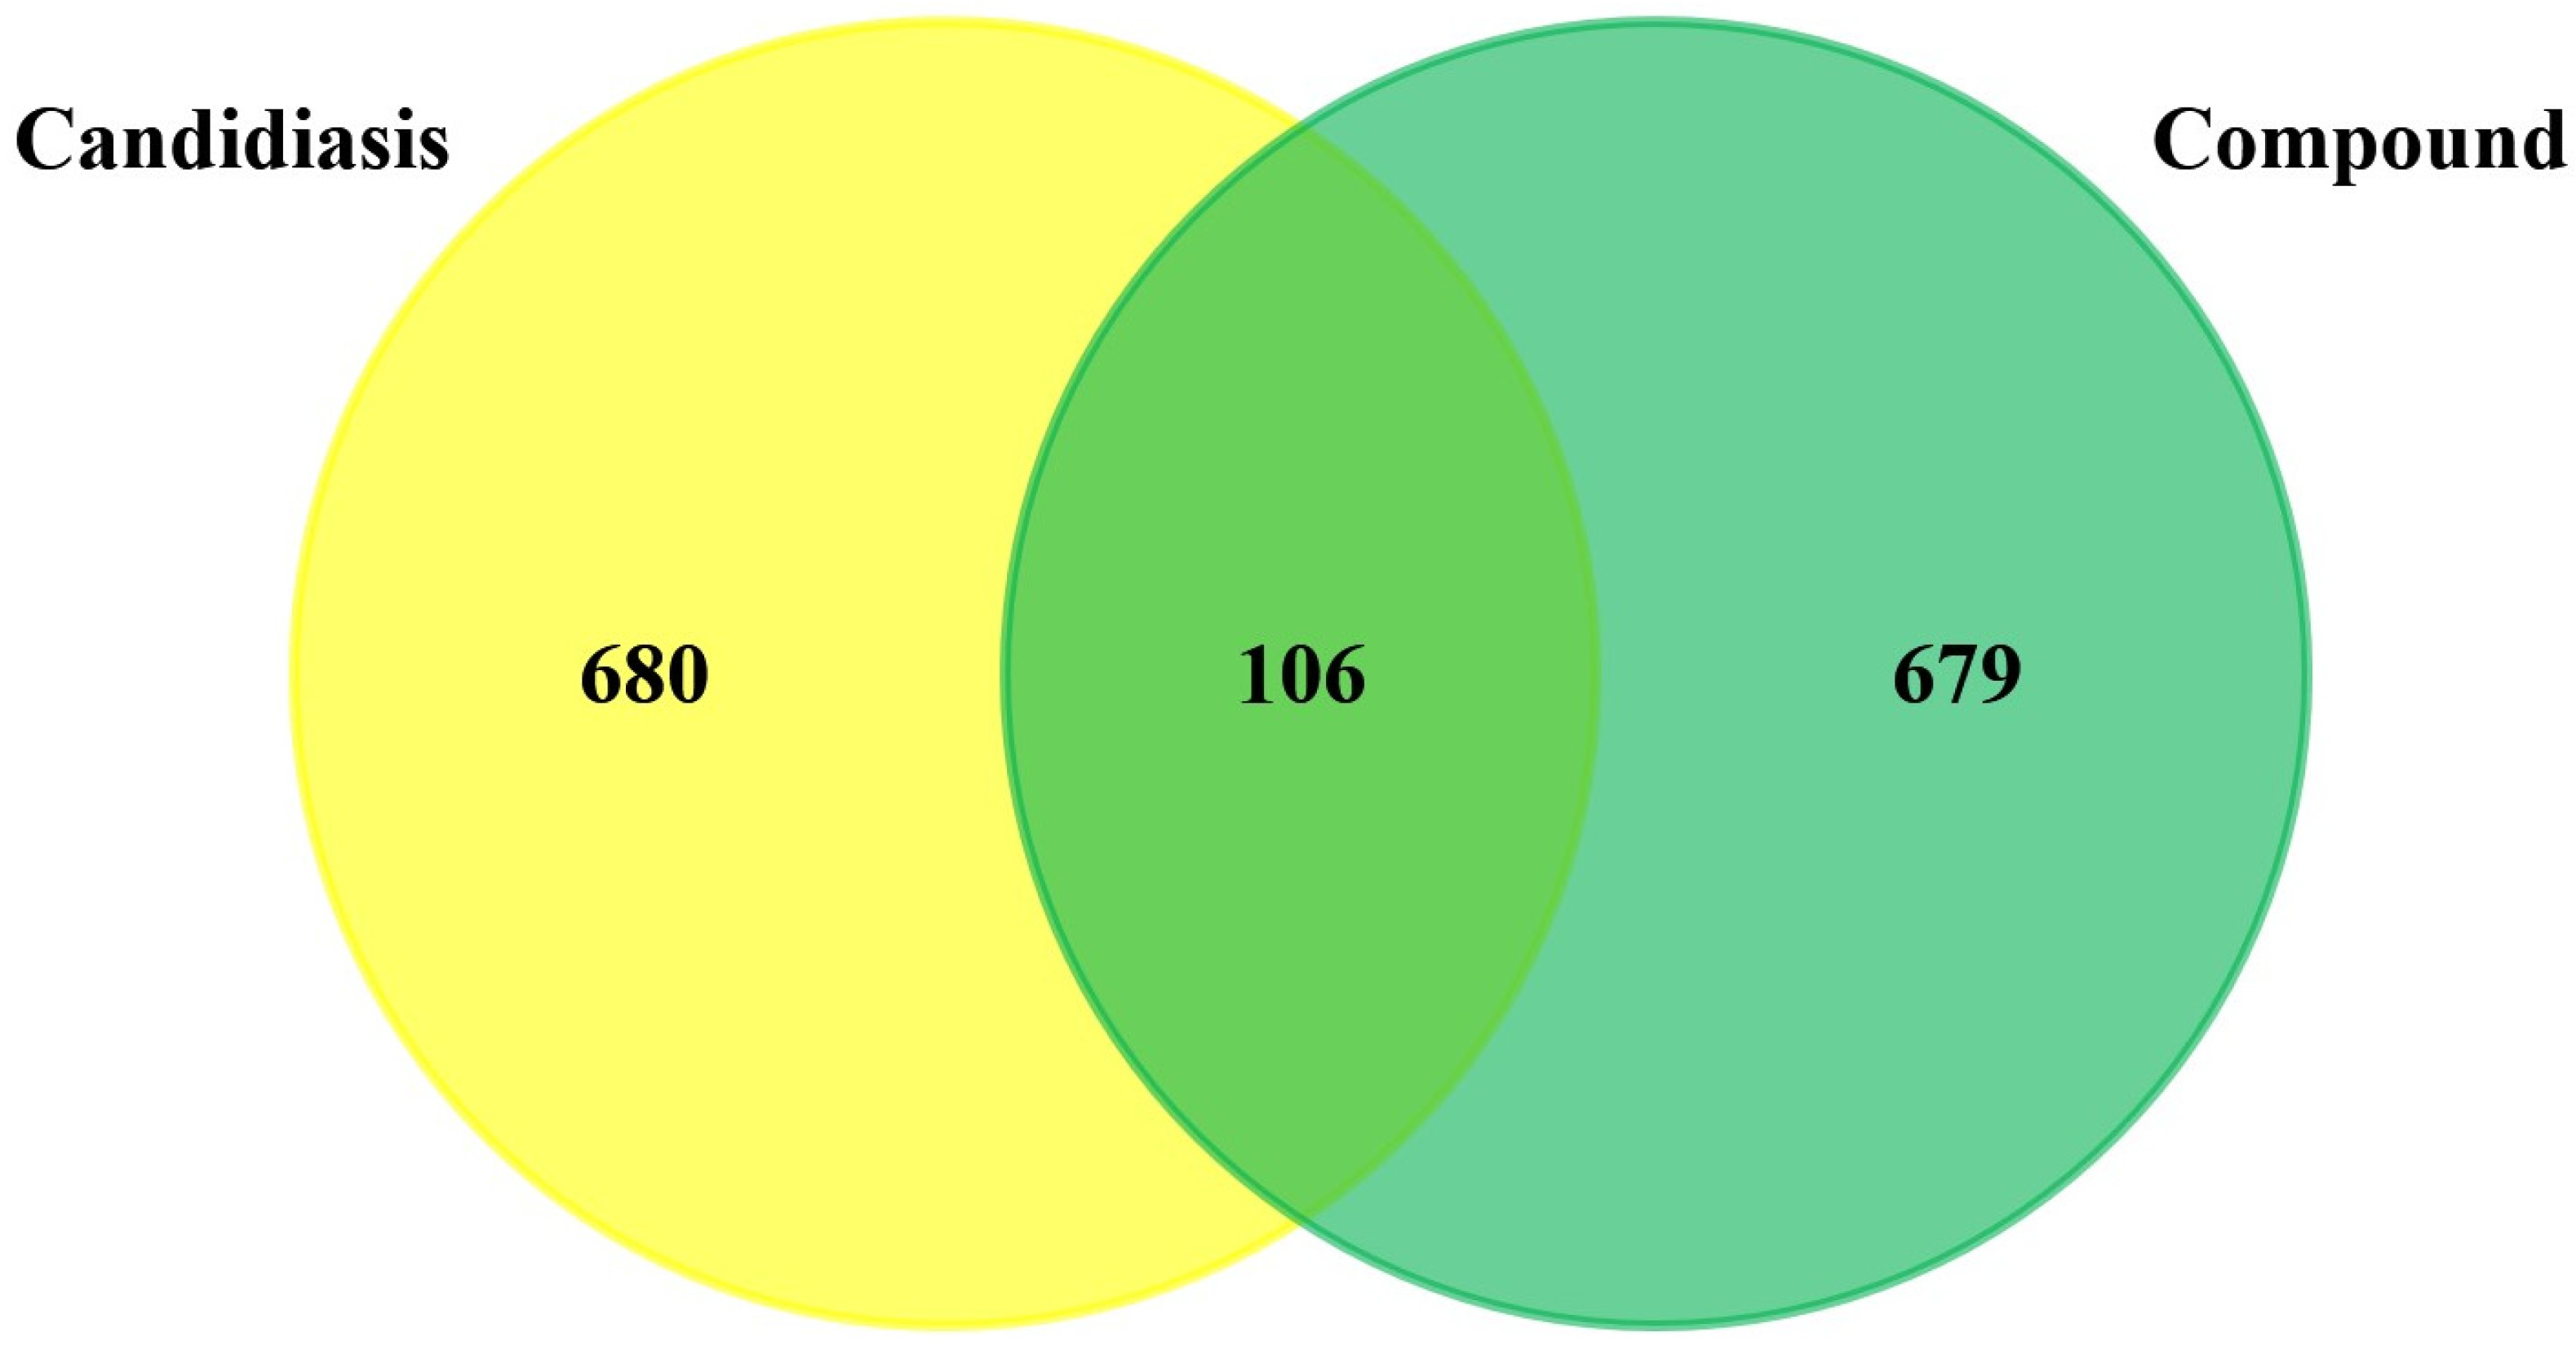

3.1. Prediction and Screening of Compound-Diseases Targets

3.2. Compound–Disease Common Target Network Construction and Analysis